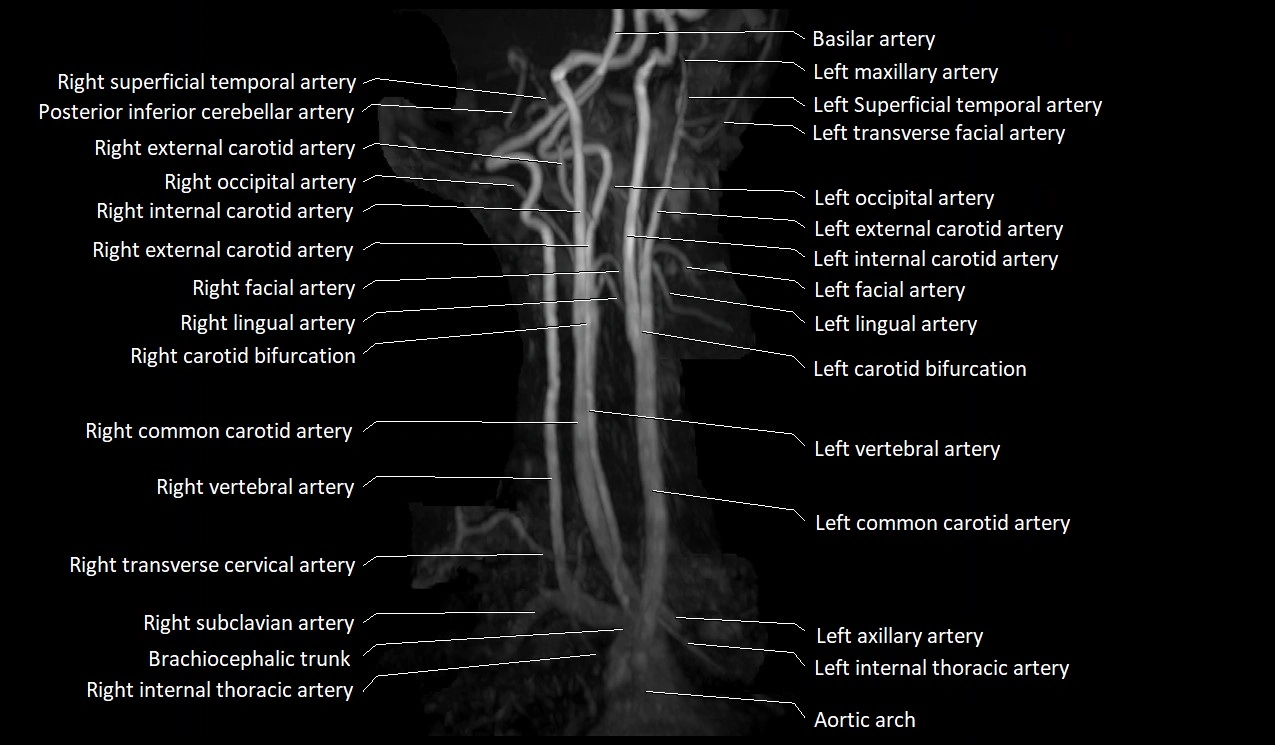

CTA (CT Angiography):

• Enhances brightly with intravenous contrast

• Easily visualized on arterial and especially venous phase images

• Shows continuity with external jugular vein or subclavian vein